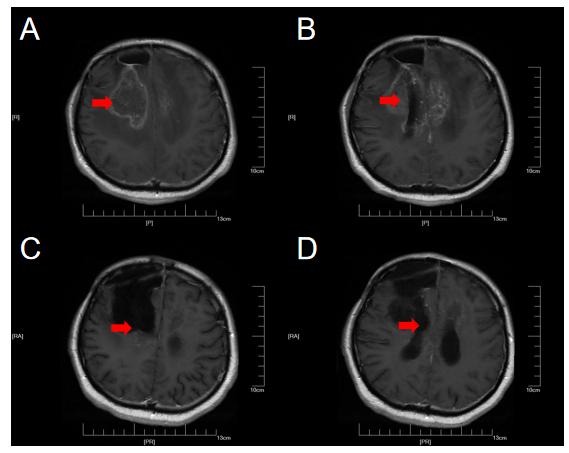

患者甲,因“癫痫大发作1次”于2018年10月6日入住上海某医院,同年10月23日在上海行手术切除治疗,术后病理为少突胶质细胞瘤(WHO III级)。术后进行规范化治疗,今年6月因右侧肢体肌力下降,复查MRI提示肿瘤复发或放射性坏死可能(下图A、B)。今年6月17日,在我院行右侧额叶异常信号切除,术后病理提示肿瘤坏死可能,患者为求下一步诊疗方案,在我院MDT门诊就诊。经胶质瘤MDT团队联合诊疗后诊断考虑为放射性坏死,予以贝伐单抗200mg q3w进行治疗,同时进行康复功能锻炼,今年9月复查MRI提示异常信号缩小(图1C,D),患者右侧肢体肌力恢复至IV-级,可在辅助物帮助下进行站立,目前治疗仍在持续中。

【图1.典型病例一:2021-09复查MRI(C,D)提示异常信号较前(A,B)明显缩小】